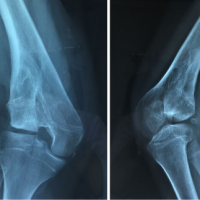

In June 2009, C.M,.(female, 48 years old) after a motorcycle accident, reported the middle third right clavicular fracture with associated multiple rib fractures and ipsilateral hemithorax (the first and second rib were free). The patient was conservatively treated with bandage “shape of eight”. After about four months from the traumatic event, we observed the displacement of the fragments and no radiographic signs of consolidation (Fig. 1a). The patient had a complex history of opiates and alcohol abuse, heavy smoking, psychopharmacological treatment for depressive syndrome, and was tested positive for HCV. Her physical examination was negative for vascular or nerve deficit of the right upper limb and no emerging central or peripheral neurological disorders, such as canalicular syndromes or cervico-brachialgy, were noted. The patient and her relatives were informed about the non-surgical option, but she preferred to undergo the intervention. The patient was then surgically treated with an open reduction internal fixation and the fracture was stabilized with a plate (Fig. 1b). The post-operative course was without complications and the patient was discharged two days later. One week after the surgery, the patient reported onset of numbness and tingling in the fingers of her right hand near the ulnar nerve. The vascular Adson test was good, and the peripheral pulses were palpable and symmetrical. After two weeks, numbness and tingling in the median nerve area occurred. Moreover, the flexor carpi radialis, the opponens pollicis muscle and the interossei muscles strength were reduced to 4/5. After about three weeks after surgery, the radial nerve deficit also appeared, with weakness of the carpi ulnaris extensor (CUE) and worsening of the deficit of the interossei muscles strength (3/5). The bone-tendon reflexes were sluggish to the upper right limb , while normal bright to the upper left and lower limbs. The patient underwent an echo color doppler examination for arterial and venous supraclavicular fossa and upper limbs, chest x-ray, right shoulder and cervical spine MRI: all of these tests seemed to exclude the presence of expansive lesions or iatrogenic damage to nerve roots of the brachial plexus or to the vascular structures. Forty days after surgery, an electromyographic and electrical conduction velocity examination was performed: we noted the almost complete denervation on the extensor digitorum muscles, right flexors of the fingers and right first interosseous neurogenic damage with denervation activity on other muscles. From clinical examination and investigations it was clear that patient was suffering from thoracic outlet syndrom most likely secondary to osteosynthesis surgery. Therefore, the patient was again subjected to surgery, 70 days after the first operation, in order to remove the means of synthesis. The not yet consolidated fracture stumps were mobilized to widen the cost-clavicular space diameters. One week after the second operation, the clinical situation seemed to improve: the digitorum communis extensor (DCE) and longus pollicis extensor (LPE) strength was 4/5; communis digitorum flexor (CDF) 3/5; longus pollicis flexor (LPF) 2/5; ulnaris carpi flexor (UCF) force 2/5; cross-finger test could not be performed; hyperhidrosis in the territory of median nerve in the palm. Two months later, the patient recovered almost completely the function of the upper right limb, the cross-finger test was allowed, and the paraesthesias and hyperhidrosis disappeared. In March 2010, the patient underwent a new intervention because the medial stump caused a skin ulcer. We remolded the proximal clavicle in the beveled way (this was not done the first time) and a new fixation was performed by plate osteosynthesis. The wound healed without further bed sore and without any changes at the neurological pattern.